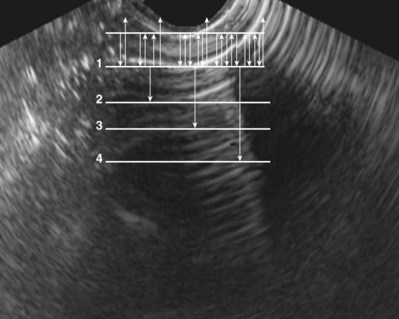

Figure 4–34 A, Transverse view of the bladder in this female patient demonstrates the uterus (U). B, Sagittal view of the bladder shows the uterus posterior to the bladder.

Figure 4–35 In this transverse view of the bladder, urine “jets” emerging from the left (arrow) and right (arrowhead) ureteral orifices are demonstrated by power Doppler.

Bladder volume can be calculated manually by obtaining measurements in the midtransverse and midsagittal planes (Fig. 4–36). Numerous studies have shown that for bladder volumes between 100 and 500 mL, such calculated volumes are within 10% to 20% of the actual bladder volume (Roehrborn et al, 1986).